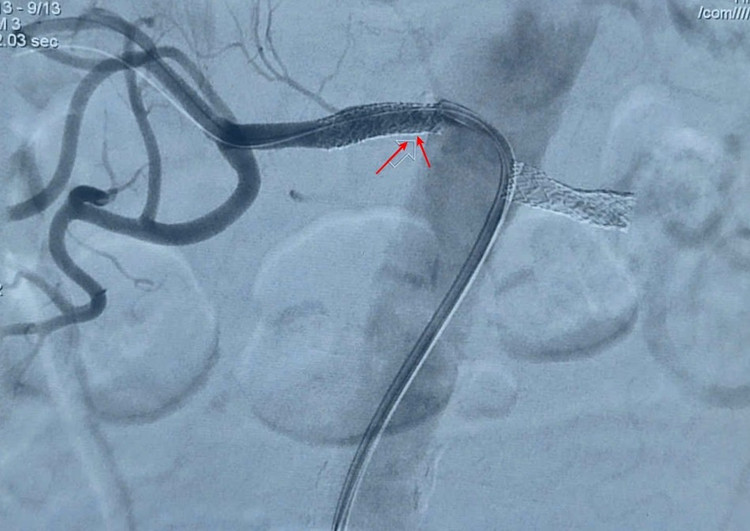

Hình ảnh can thiệp đặt stent động mạch thận 2 bên qua phim DSA - Ảnh BVCC

Với sự hỗ trợ của hệ thống chụp mạch số hóa xóa nền hai bình diện (DSA) hiện đại, bác sĩ đã luồn ống qua đường động mạch đùi đến vị trí tổn thương, nong bóng đoạn hẹp khít và đặt stent động mạch thận hai bên, tái thông dòng chảy nuôi thận. Toàn bộ quá trình can thiệp diễn ra an toàn, ít đau, giúp phục hồi lưu thông máu về thận một cách hiệu quả.

Kíp can thiệp do ThS.BS Ngô Văn Tuấn, Trưởng khoa Tim mạch trực tiếp thực hiện, được tiến hành theo chiến lược hai thì, mỗi thì xử lý một bên động mạch thận, cách nhau 10 ngày để đảm bảo an toàn cho người bệnh.